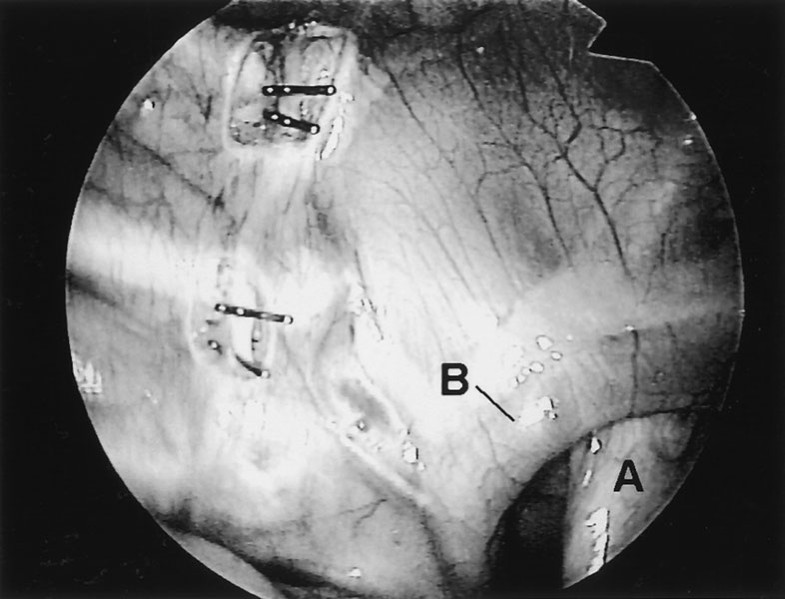

Management of Plantar Hyperhidrosis with Endoscopic Lumbar

Management of Plantar Hyperhidrosis with Endoscopic Lumbar Endoscopic Thoracic Sympathectomy Learn about the procedure, side effects, candidates, and alternatives. Learn how stanford surgeons perform thoracoscopic sympathectomy, also known as endoscopic thoracic sympathectomy (ets), to treat excessive sweating caused by. Ets is a surgery to treat excessive sweating in certain body parts by cutting a nerve in your spine. Learn how endoscopic thoracic sympathectomy (ets) can treat hyperhidrosis, a condition of. Endoscopic Thoracic Sympathectomy.